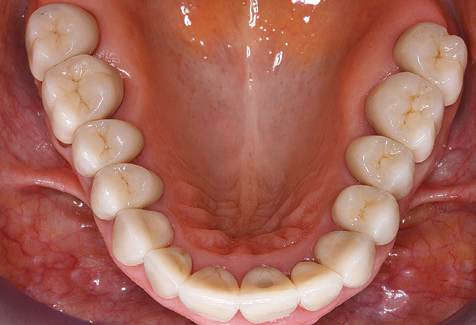

A causa della presenza di problematica parodontale, SPT è stata eseguita ogni tre mesi nei primi anni successivi all'inserimento. Il paziente ha dimostrato un alto grado di motivazione e una buona costanza. Le profondità di tasca registrate ogni anno hanno rivelato una situazione parodontale stabile con un indice BOP inferiore al cinque per cento. Sulla base della situazione parodontale stabile e della buona collaborazione da parte del paziente, l'intervallo di richiamo è stato esteso ogni sei mesi a partire dal sesto anno dalla fase della funzione protesica. A seguito della modifica dell'intervallo di richiamo, la rispettiva documentazione annuale dello stato parodontale ha continuato a rivelare una situazione parodontale stabile senza aumento della profondità della tasca e un indice BOP inferiore al cinque per cento (Fig. 2a eb).

Fig. 2: Le profondità delle tasche registrate ogni anno con SPT semestrale non mostrano una tendenza in aumento e un indice BOP inferiore al 5% con una situazione parodontale in gran parte priva di infiammazione. a) status PERIO nel 2011 (dopo cinque anni con impianti). b) status PERIO nel 2016 (dopo dieci anni con impianti).